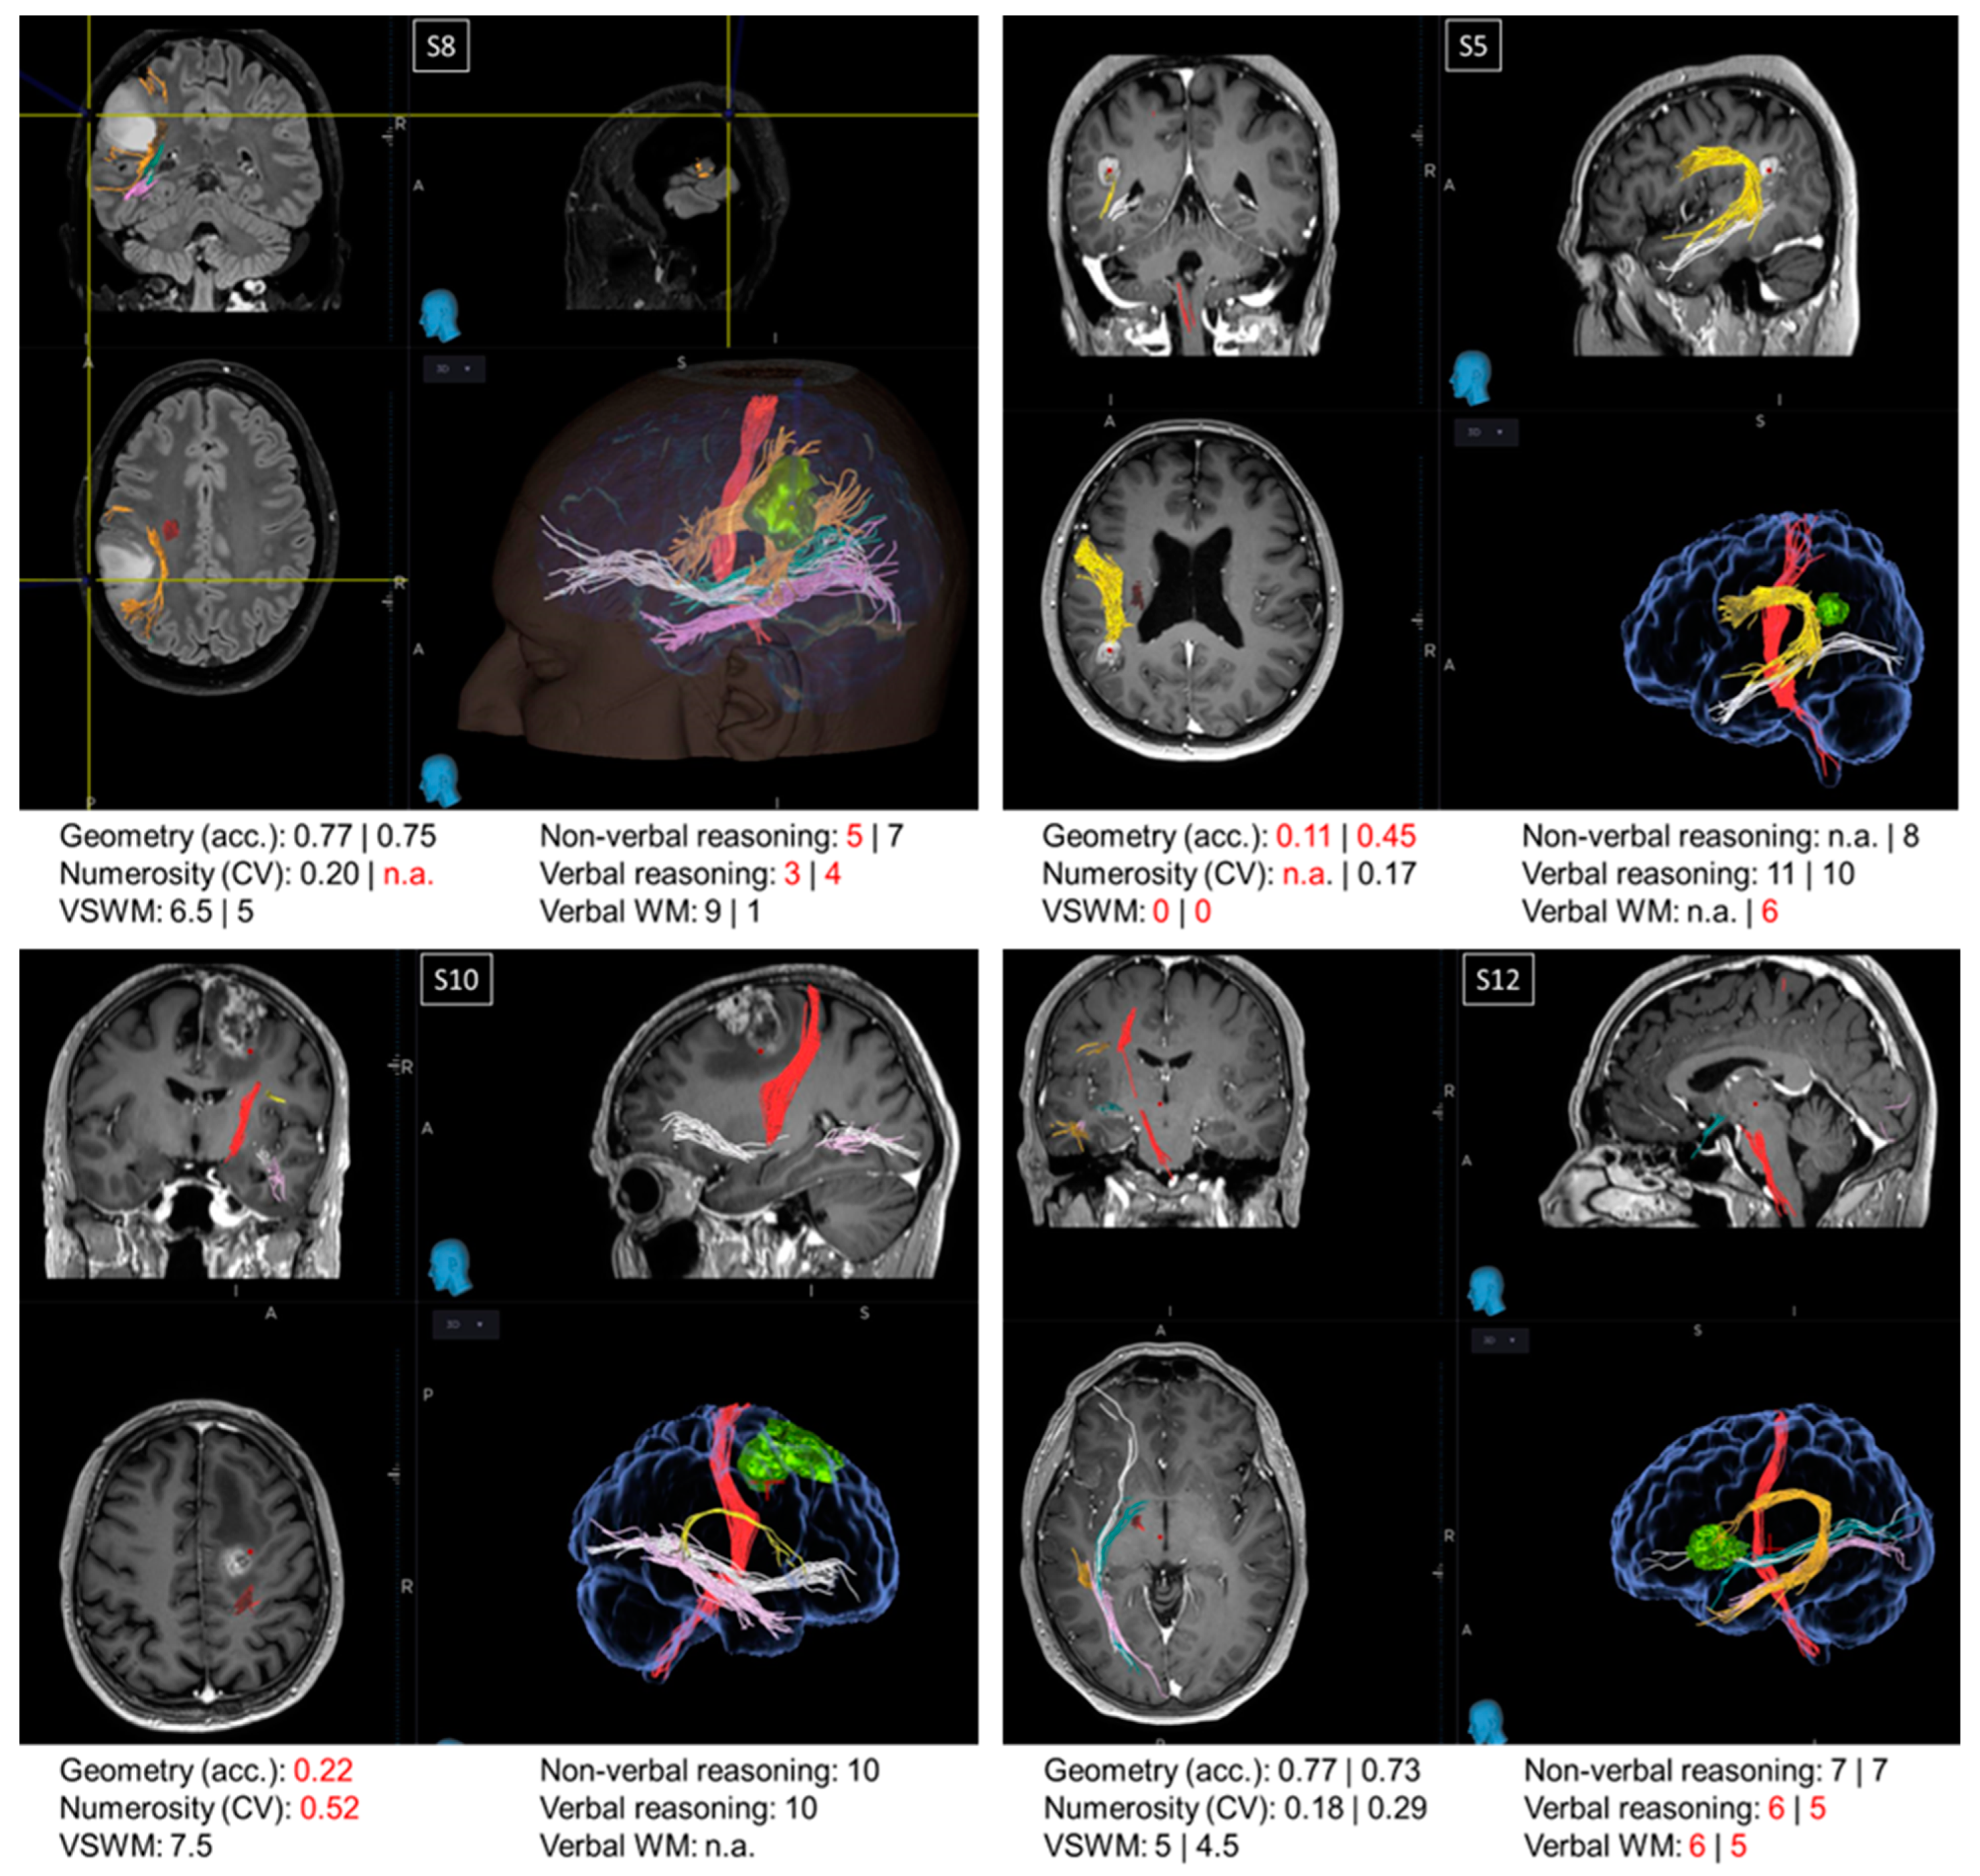

Oncological lesions often compromise a large portion of the patients’ brain, making the relation between the loss (or preservation) of a certain function and the functionality of a specific region hard to trace. For this reason, from a pool of more than 400 neuro-oncological patients operated on at the Neurosurgical Department of the University Hospital of Florence over almost two years, we selected 16 patients with small lesions located in precise intralobular anatomical regions. Although this selection resulted in a relatively restricted sample size, it offered the opportunity to evaluate single cases, which is often standard practice in neuropsychology. Many authors consider single case studies as a powerful neuropsychological technique [51] as they offer the opportunity for in-depth testing of the brain lesions of one or a few patients alongside a precise assessment of the cognitive abilities impaired as a consequence of the brain circuits’ disruption. Indeed, many of the most crucial discoveries in the field of neuropsychology have been gathered via single case studies through the description of single or double dissociations of the cognitive functions. In this section, we describe the cognitive profile of four patients (Figure 3). Examination of the first three single cases (S5, S8, and S10) suggested that the non-symbolic geometry test measures abilities additional to those measured by non-verbal reasoning and non-verbal working memory tests. The last single case (S12) is discussed because it was particularly informative for the localization of the regions crucial to perform the non-symbolic geometry test accurately.

Figure 3.

Single cases. Images from the NeuroNavigation system, Medtronic (reading left image_left side/right image_right side): MRI images displaying the lesions and scores in neuropsychological and psychophysical tests in patients S8, S5, S10, and S12. When two values are present, the first refers to the score before the surgery and the second refers to the score obtained after the surgery. Scores below the normative value are marked in red. Major fibers obtained by MRI DTI before the surgery are color-coded as follows: red: corticospinal tract; orange/yellow: arcuate fasciculus; green: optic radiations; pink: inferior longitudinal fasciculus (ILF); white: inferior fronto-occipital fasciculus (IFOF).

Patients S5, S8, and S10. Patient S8 and patient S5 exhibited a double dissociation between their scores in the non-symbolic geometry and non-verbal reasoning tests. Before surgery, patient S8, with a parietal lesion, performed the non-symbolic geometry test with very high accuracy; however, their performance in the non-verbal reasoning test was below the normative value. On the other hand, patient S5, also exhibiting a parietal lesion, was very inaccurate in the non-symbolic geometry test both before and after surgery, despite scoring within the normative range in the non-verbal reasoning test after the surgery (scores before the surgery not available). While the comparison between these two patients suggests a dissociation between non-symbolic geometry and non-verbal reasoning, performance on the non-symbolic geometry test in these patients could potentially be fully explained by the functionality of their visuo-spatial working memory, which was spared in S8 and impaired in S5, both before and after the surgery. This means that, if these two patients simply relied on their visuo-spatial working memory, they would have likely scored the same in the non-symbolic geometry test, without necessarily having grasped that the square was moving following a geometrical trajectory (rather than randomly). However, this explanation does not hold when considering patient S10, who had a frontal lesion. Similarly to patient S5, S10 performed poorly on the non-symbolic geometry test despite normal non-verbal reasoning scores, but in contrast to S5, patient S10 also had a good visuo-spatial working memory, although it was not sufficient to perform the non-symbolic geometry test well.

Patient S12. Frontal patients were among the most impaired in the non-symbolic geometry test, except for patient S12, who performed this test with accuracies within the normative range, both before and after surgery. Their visuo-spatial working memory and non-verbal reasoning scores were within the neurotypical range, whereas their verbal reasoning and verbal working memory were impaired. This is in line with their lesion’s location, which was circumscribed to the language areas in the inferior frontal gyrus. Interestingly, the lesion did not extend to the region dorsal to BA44, which is a region selectively involved in geometrical sequence complexity independent of memory demand [46], possibly explaining why non-symbolic geometry was spared in this patient.